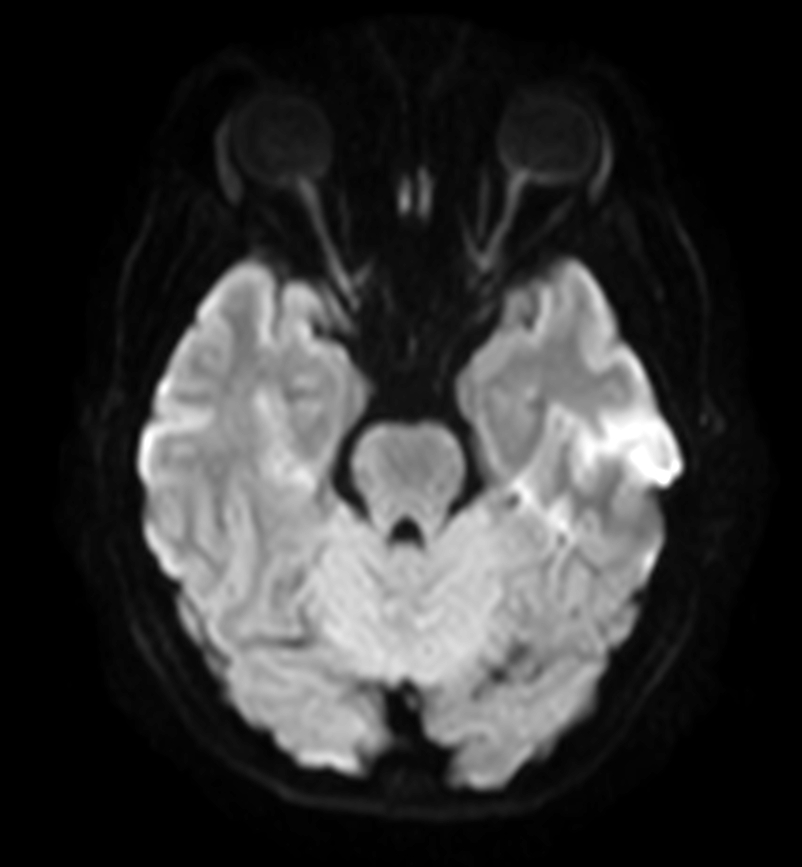

DWI (b1000)